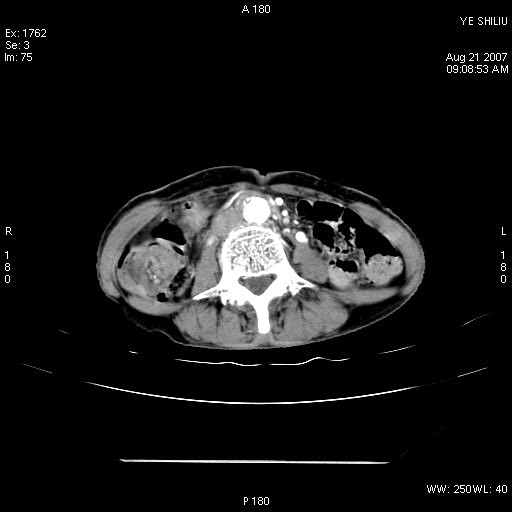

回盲部腺癌

患者,女,74岁,腹痛一周。开始为脐周疼痛,后转移至右下腹。治疗经过:门诊拟急性阑尾炎收内科治疗,b超示胆囊结石、胆囊炎转外科。拟行胆囊切除术前检查ct。